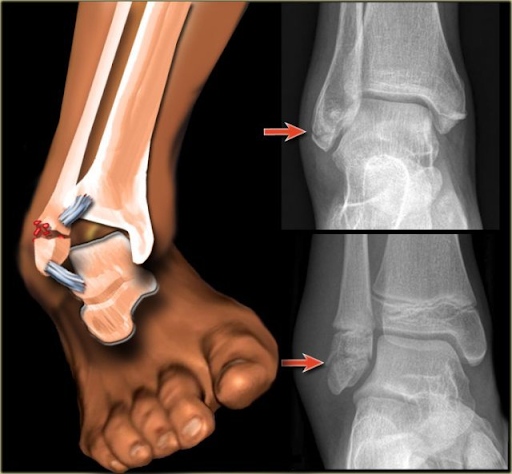

3. Achilles Tendon Rupture

Tendon Achilles (belakang betis sampai tumit) robek karena tekanan besar atau gerakan mendadak.